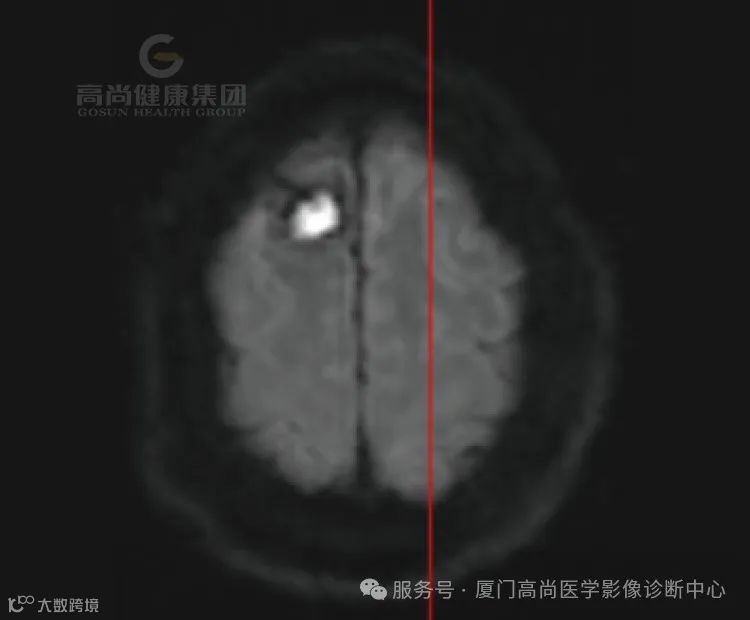

患者代诉左侧肢体无力半月余,既往高血压史。

1.右侧丘脑、基底节、放射冠区病灶,考虑脑出血(亚急性期)并破入右侧脑室,中线结构局部左偏,请结合临床。

2.右侧额叶团状稍高异常信号影,相邻右侧额骨局部孔状影,请结合临床,建议复查。

3.脑白质病变(Fazekas评分,3分)。